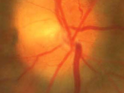

Leonid Skorin, Jr., DO, MS, OD

The potential for ocular side effects in patients taking selective phosphodiesterase (PDE) 5 inhibitors has been documented. The most common visual symptoms associated with the PDE 5 inhibitors are the...